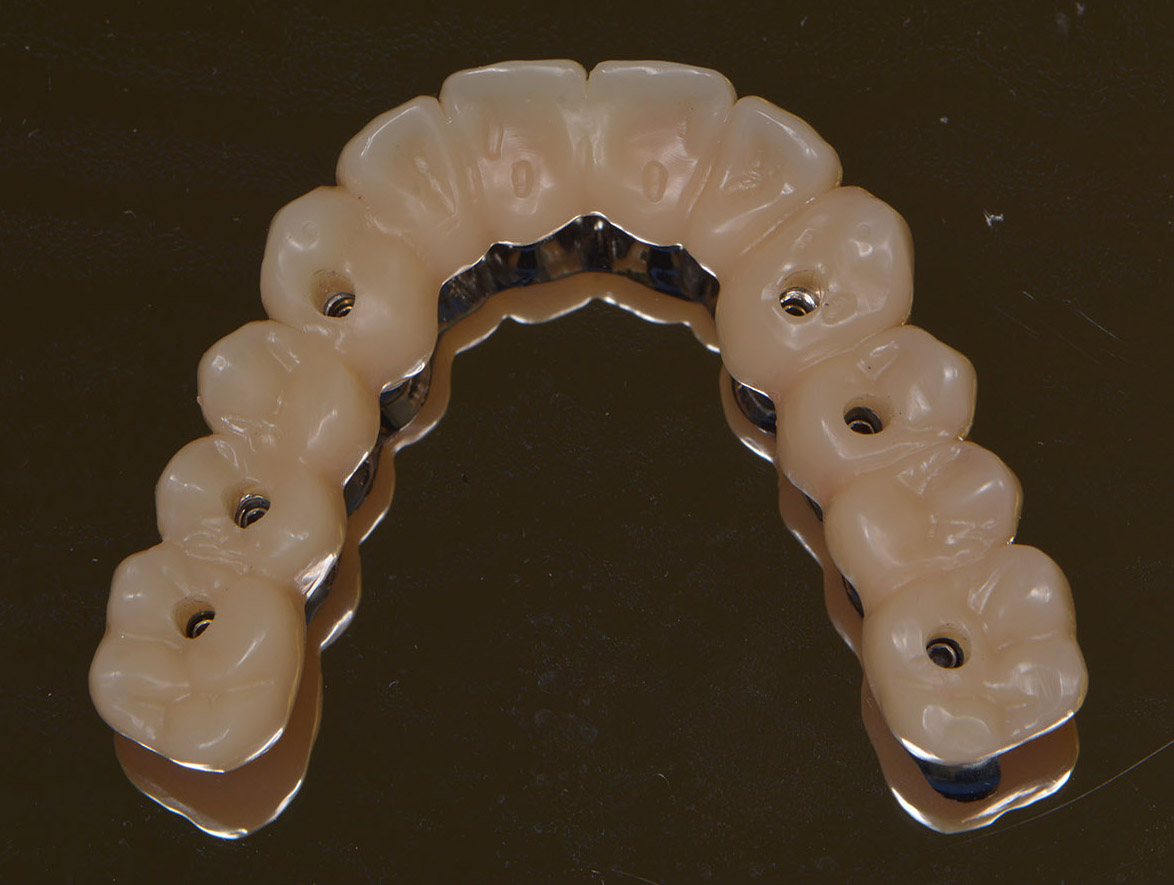

Il sistema permette al clinico di progettare al computer la posizione e la dimensione esatta degli impianti prima dell’intervento chirurgico utilizzando la ricostruzione tridimensionale (3D) di una zona o dell’intera arcata dentale per poi richiedere ad un centro specializzato la costruzione di una guida chirurgica estremamente precisa che permetterà di eseguire un intervento atraumatico.

Questa tecnica consente inoltre la realizzazione di una protesi immediata ancora prima di effettuare l’intervento.